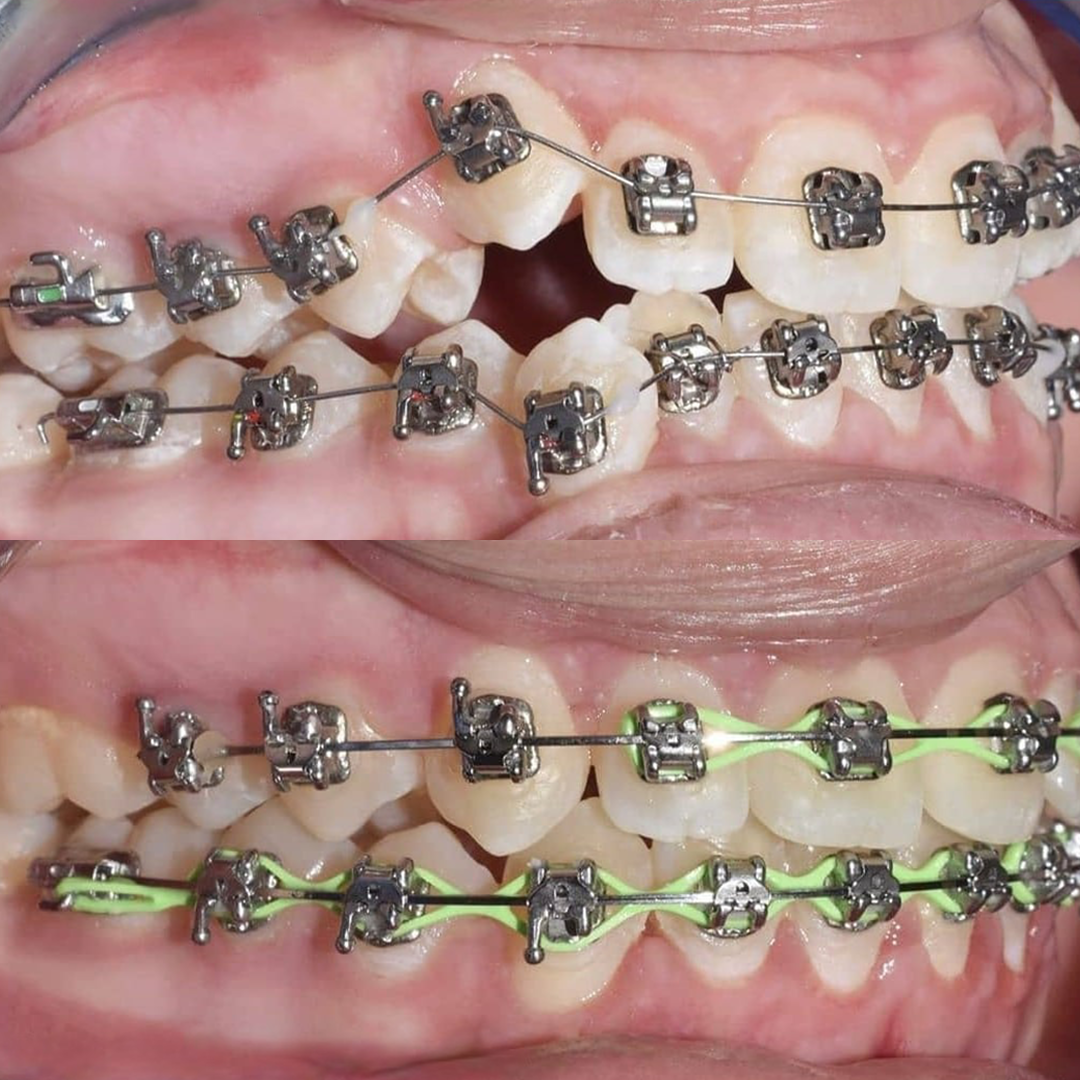

Результат коррекции металлической брекет-системой

Результат коррекции самолигирующей брекет-системой

Результат коррекции керамической брекет-системой